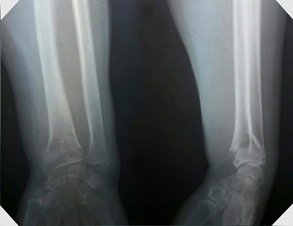

При переломах променевої кістки застосування сучасних імплантів дає можливість найшвидшого відновлення функції променезапясткового суглобу.